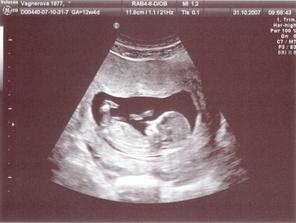

26.10.2007 - ulrazvuk ve 12 tt, vše v pořádku, máme 6,46cm od hlavy k zadečku a melem sebou o 106 :o) 31.10.2007 - jsme byli na NT+ biochemický screening (projasnění šíje 1,0 cm a krevní testy dopadly dobře ;o)